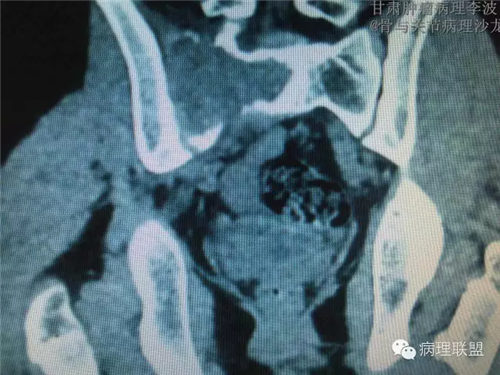

M/14 骶骨骨肉瘤-张惠箴讲解

病例由甘肃肿瘤病理 李波 提供,致谢。